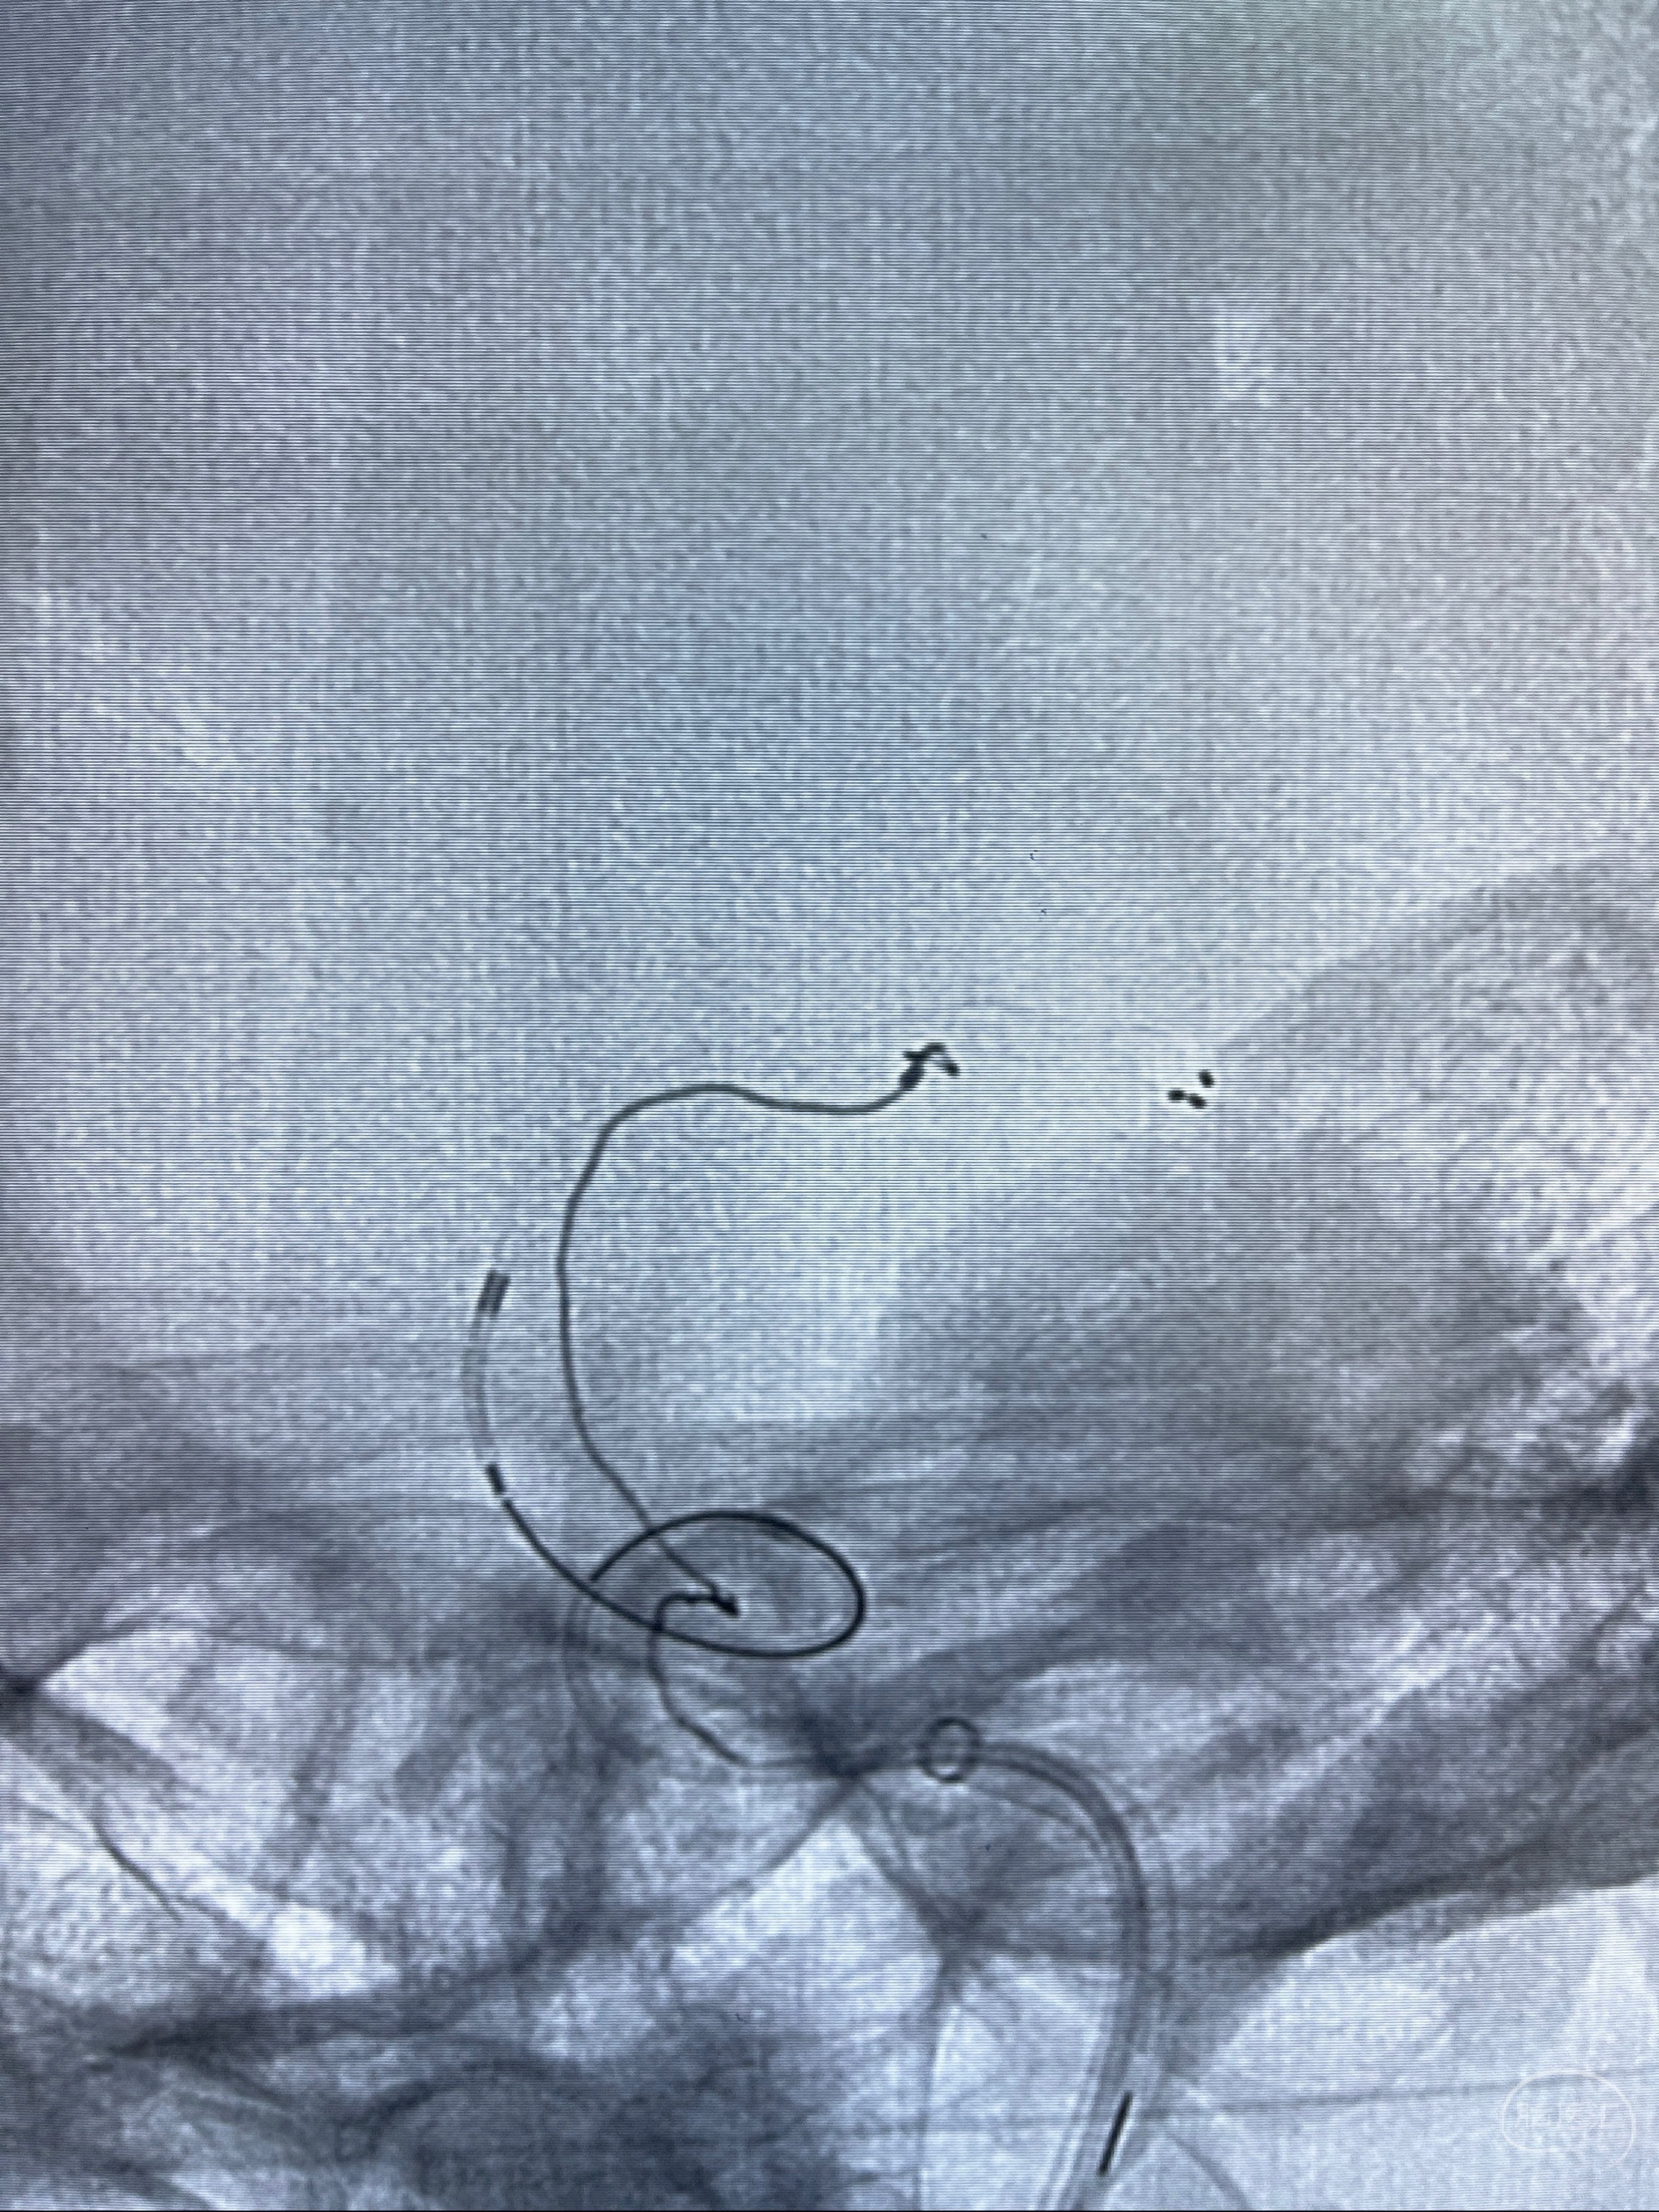

2023-08-14DSA:

左侧大脑中动脉动脉瘤,约2.6-2.8-3.4-2mm大小(瘤颈部、瘤体部、瘤高)